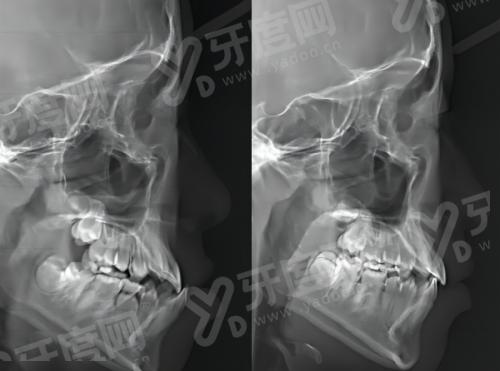

数字化种植技术:采用3D导板精细种植,通过口腔CT扫描获取患者口腔三维数据,术前模拟种植路径,术中精细植入种植体,减少手术创伤,缩短愈合时间,适用于单颗、多颗及半口/全口缺失牙患者。